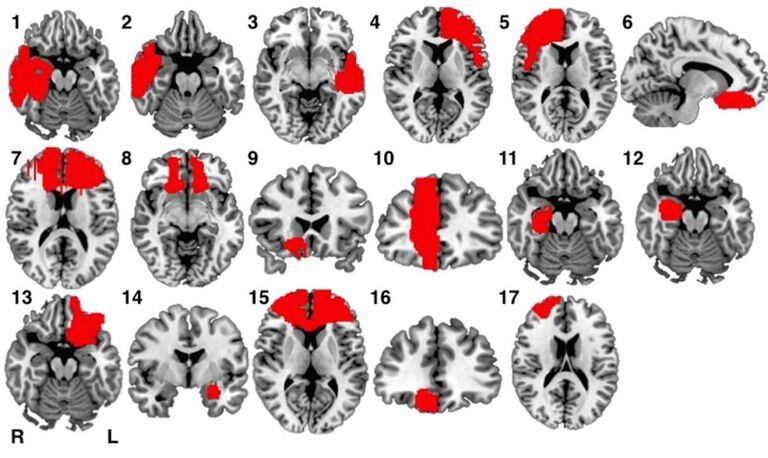

O primeiro resultado da pesquisa pode surpreender: em nenhum dos casos a lesão exata coincide. “Acho que é difícil de entender inclusive para neurologistas e neurocientistas”, diz o professor de neurologia da Universidade Vanderbilt (EUA) e principal autor do estudo Ryan Darby. “Nossa hipótese é a de que as lesões ocorreram em partes diferentes da mesma rede cerebral conectada”, explica.

Apesar de a localização das lesões não se repetir nenhuma vez, em todos os casos detectou-se que as regiões lesionadas pertenciam à mesma rede de conexões neuronais, a da tomada de decisões morais. “Para a conduta moral, mais relevante do que uma região concreta é a interação dentro de uma rede de diferentes regiões cerebrais, o que explica a mudança de conduta”, comenta Darby.